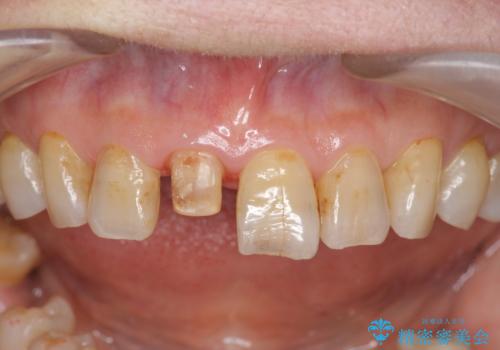

- 前歯を転倒で受傷し、審美性の回復を求めて来院されました。

近医で暫間的なコンポジットレジン修復が為されていましたが、色調に不満があるということでした。

色調の変化が少なく、長期的な予後を見込めるジルコニアクラウンで天然歯を模した審美性の回復を計画します。